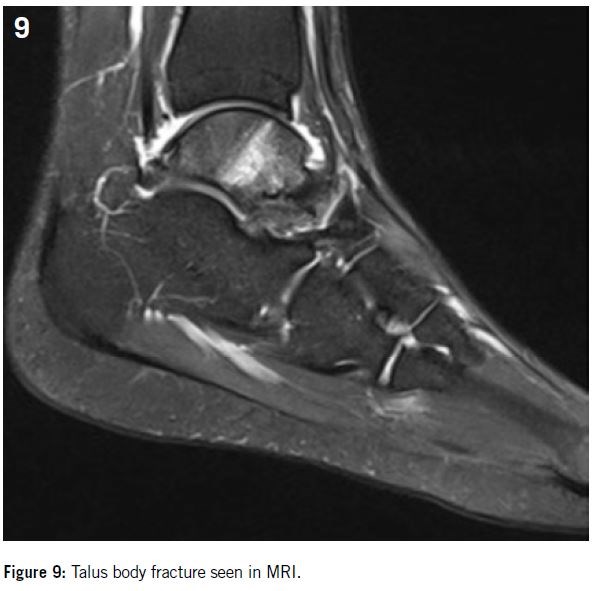

Talus fracture: this BSF is rare and generally located at the level of the head of the Talus and often associated with a damaged talar dome, navicular bone, or calcaneus29. Runners and gymnasts are the athletes the most at risk34,40.

Clinically, patients complain of a non-traumatic pain in the midfoot or sinus tarsi. Sometimes an effusion can be observed39.

X-rays are normal in the great majority of cases, whereas MRI allows diagnosis in more than 80% of cases (Figure 9).

This fracture is rarely displaced, so its classification as a high-risk fracture is still controversial but due to the low vascularization of the talus, the significant risk of delayed union, and the high proportion patients unable to resume sport at the same level, for athletes surgical fixation is recommended even if the fracture is not displaced6,8,39 (Figure 10).